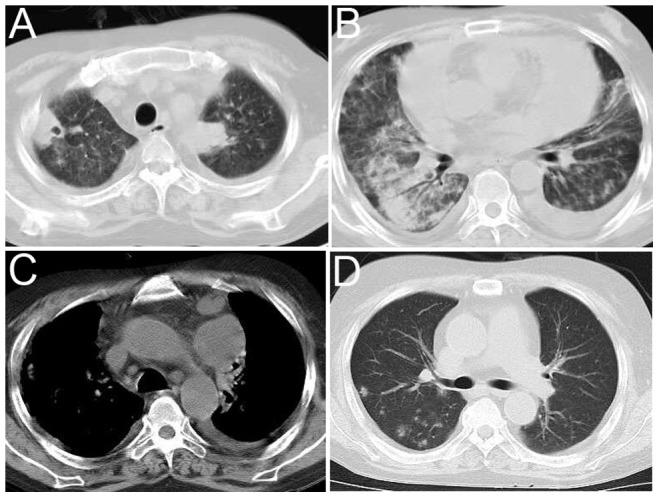

The study included 17 patients who were diagnosed with PN. Of these patients, 4 developed concomitant disseminated disease. A male predominance was observed among the patients with PN (76.47%). The most common risk factors were corticosteroid therapy (64.71%), diabetes mellitus (29.41) and chronic lung disease (23.53%). Cough and fever were the most common symptoms (94% and 71%, respectively). One or more nodules or masses (82.35%) and consolidations (58.82%) were the most frequent radiologic abnormalities, and cavitation mostly occurred within two weeks. The median time to diagnosis was 25 days. Overall, the mortality rate was 18.75% for PN, and death was most frequent among patients who received immunosuppressive drugs. For the patients with central nervous system involvement, the mortality rate was 50%.

PN remains a rare opportunistic infection that mainly affects immunocompromised patients. A high clinical index of suspicion is necessary for an early diagnosis and timely treatment in immunocompromised patients who present with new nodules or masses evolving into cavitation in a short amount of time.

本研究纳入了17例确诊为PN的患者。其中,4例并发播散性疾病。PN患者中男性占优势(76.47%)。最常见的危险因素为糖皮质激素治疗(64.71%)、糖尿病(29.41%)和慢性肺部疾病(23.53%)。咳嗽和发热是最常见的症状(分别为94%和71%)。一个或多个结节或肿块(82.35%)和实变(58.82%)是最常见的影像学异常,空洞形成大多发生在两周内。诊断的中位时间为25天。总体而言,PN的死亡率为18.75%,死亡在接受免疫抑制药物治疗的患者中最为常见。对于中枢神经系统受累的患者,死亡率为50%。

PN仍然是一种罕见的机会性感染,主要影响免疫功能低下的患者。对于出现新的结节或肿块并在短时间内发展为空洞的免疫功能低下患者,早期诊断和及时治疗需要高度的临床怀疑指数。